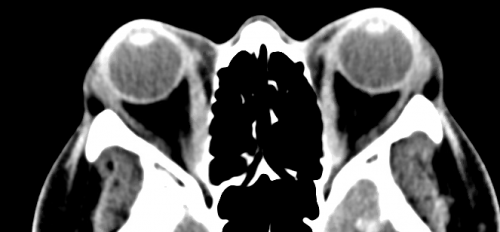

Imaging

Computed tomography (CT) scans and magnetic resonance imaging (MRI) serve as the main diagnostic tools to further characterize the proptosis. Features visualized on imaging that pertain to the location and specificity of swelling, as in the case of orbital pseudotumor vs thyroid eye disease, will help to diagnose and treat the underlying cause of the disease. However, there will remain cases that, due to clinical similarities, will necessitate tissue biopsies to confirm a diagnosis.[1][8]

Furthermore, there is utility in orbital and head imaging using CT and/or MRI when planning for a customized orbital decompression because it allows for visualization of the position and thickness of various orbital bones and surrounding structures. Imaging also adds practical value if a surgeon decides to utilize stereotactic guidance during surgery. This preoperative imaging allows for reconstruction of a three dimensional image of anatomy that corresponds to an external guidance system. This guidance system can be used to compare the 3D model against the real surgical field to assist with real-time spatial awareness of structures that may not be visually apparent during surgery. Vascular lesions may warrant arteriography and venography.

In conjunction with functional ocular testing and a complete clinical exam, imaging such as MRI and CT scans should be employed to give a visual representation of the existing anatomical abnormalities and potential routes for surgical planning. MRI and CT imagery should include the extraocular muscles, orbital fat compartment, orbit, paranasal sinuses, and optic nerve appearance.[25] The functional ocular exams congruent with imaging will aid the surgeon in disclosing the severity of compression within the ocular orbit.